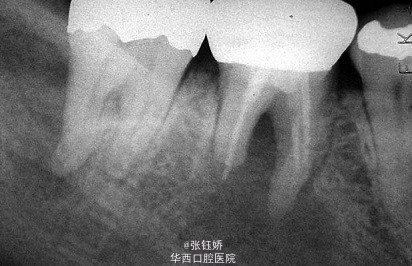

女,56岁,自觉左下磨牙区敏感不适,X线片示36牙已根充,远中根管超填,近中根管欠填,根管预备显示近中根管下段钙化,根尖周见较大暗影。考虑到患者牙合间距离很小不符合根尖手术适应症,故拟行意向性牙再植术。